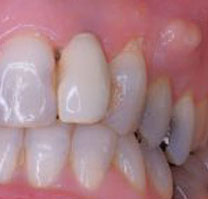

Hình: áp xe ở răng cửa hàm trên. Trường hợp này phải điều trị khẩn bằng cách rạch abcess để thoát mủ.

Hình: áp xe do phục hình răng sứ không tốt, gây viêm và nhiễm trùng tủy răng. Sẽ rất khó giữ lại được một chiếc răng bị nhiễm trùng nặng như vậy.